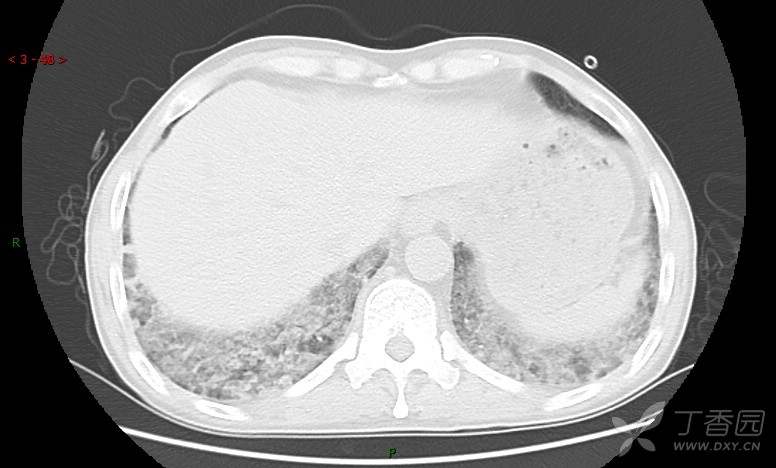

地图+铺路石征=PAP?那升高的CEA怎么说(病例3连发,附其他2例链接)

患者男,42岁,咳嗽半年余,加重伴憋喘2月余。

患者半年余前无明显诱因出现间断咳嗽,干咳为主,偶咳少量黄白痰,剧烈咳嗽或运动后可出现轻度憋喘,无高热、脓臭痰,无胸痛、咯血及晕厥,无低热乏力及盗汗,无心前区压榨感及夜间阵发性呼吸困难,初未在意,未予正规诊治。2月余前患者自觉上述症状较前加重,咳嗽、憋喘明显,黄白色粘痰略有增多,伴有发热,热前伴有畏寒、寒战,体温最高达38.9℃,先后就诊多家医院,入住重症监护室,未行气管插管,考虑“重症肺炎”,给予“美罗培南、复方磺胺甲噁唑”等药物抗感染,“卡泊芬净”抗真菌,并给予“甲泼尼龙”等药物治疗35天,经治疗后症状好转于2018-04-02出院。患者自出院后仅应用中药治疗(具体不详),并给予家庭氧疗,平素仍有间断咳嗽,咳少量黄白色粘痰,活动后憋喘明显,活动耐量差,以卧床为主。